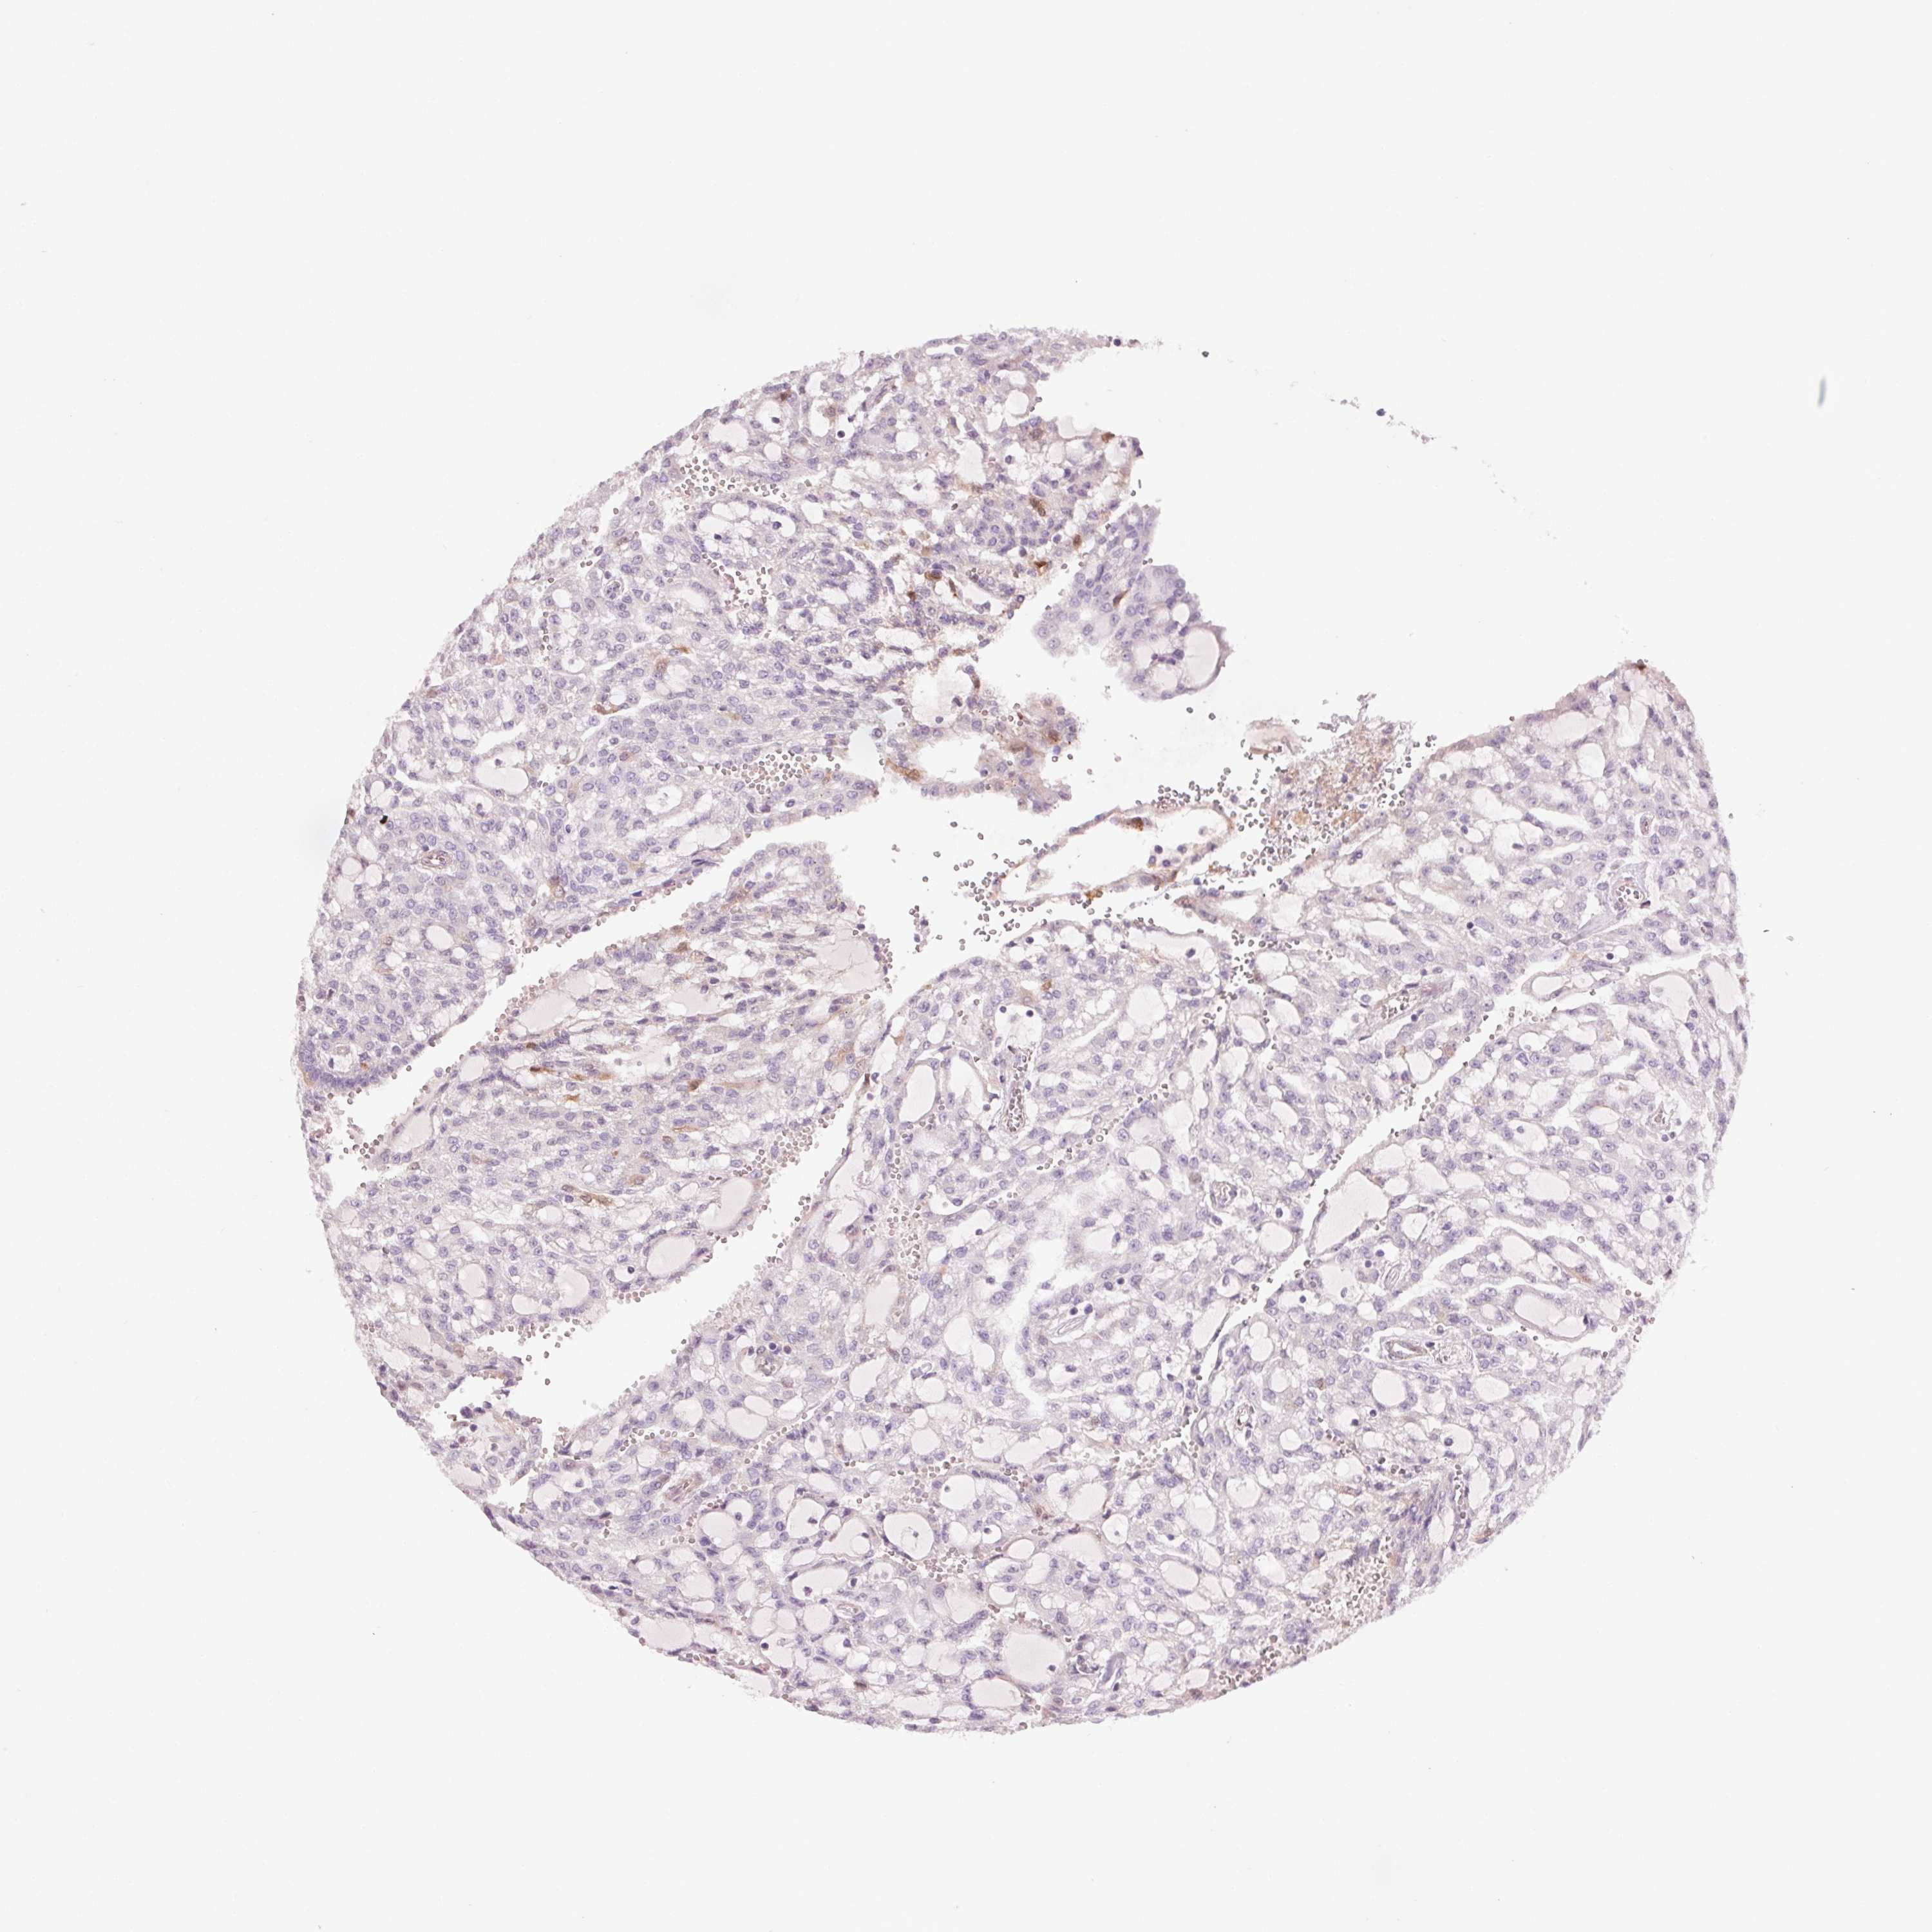

KIDNEY RENAL CLEAR CELL CARCINOMA (VALIDATION) - Interactive survival scatter ploti

The Survival Scatter plot shows the clinical status (i.e. dead or alive) for all individuals in the patient cohort, based on the same data that underlies the corresponding Kaplan-Meier plots. Patients that are alive at last time for follow-up are shown in blue and patients who have died during the study are shown in red.

The x-axis shows the expression levels (FPKM) of the investigated gene in the tumor tissue at the time of diagnosis. The y-axis shows the follow-up time after diagnosis (years). Both axes are complimented with kernel density curves demonstrating the data density over the axes. The top density plot shows the expression levels (FPKM) distribution among dead (red) and alive patients (blue). The right density plot shows the data density of the survived years of dead patients with high and low expression levels respectively, stratified using the cutoff indicated by the vertical dashed line through the Survival Scatter plot. This cutoff is automatically defined based on the FPKM cutoff that minimizes the p-score. The cutoff can be changed by dragging the vertical line or by entering a cutoff value in the square labeled "Current cut-off".

Under the Survival Scatter plot the p-score landscape (black curve; left axis) is shown together with dead median separation (red curve; right axis). Dead median separation is the difference in median mRNA expression between patients who have died with high and low expression, respectively. It is calculated as follows: median FPKM expression of dead patients with high expression - median FPKM expression of dead patients with low expression. This is intended to aid the user in visually exploring custom cutoffs and the associated p-scores and dead median separation.

Individual patient data is displayed and can be filtered by clicking on one or more of the category buttons on the top of the page. Categories describing expression level and patient information include: high, low, alive, dead, female, male and tumor stages. The scale of the x-axis can be toggled between linear and log-scale by clicking on the "x log" button. Mouse-over function shows TCGA ID, patient information and mRNA expression (FPKM) for each patient.

& Survival analysisi

Kaplan-Meier plots summarize results from analysis of correlation between mRNA expression level and patient survival. Patients were divided based on level of expression into one of the two groups "low" (under cut off) or "high" (over cut off). X-axis shows time for survival (years) and y-axis shows the probability of survival, where 1.0 corresponds to 100 percent.

HHLA2 is not prognostic in Kidney Renal Clear Cell Carcinoma (validation)

Best expression cut offi

Based on the FPKM value of each gene, patients were classified into two groups and association between prognosis (survival) and gene expression (FPKM) was examined. The best expression cut-off refers the FPKM value that yields maximal difference with regard to survival between the two groups at the lowest log-rank P-value. Best expression cut-off was selected based on survival analysis .

When clicking on this number, the vertical dashed line indicating cut-off, the interactive survival plot, and the Kaplan-Meier curve will be adjusted to show results based on the best expression cut-off.

: 22.48

P scorei

Log-rank P value for Kaplan-Meier plot showing results from analysis of correlation between mRNA expression level and patient survival.

N/A

TCGA RNA samplesi

RNA-seq data is reported as average FPKM (number Fragments Per Kilobase of exon per Million reads), generated by the The Cancer Genome Atlas (TCGA) .

Normal distribution across the dataset is visualized with box plots, shown as median and 25th and 75th percentiles. Points are displayed as outliers if they are above or below 1.5 times the interquartile range. FPKM values of the individual samples are presented next to the box plot.

Average pTPM 78.8

Number of samples 100